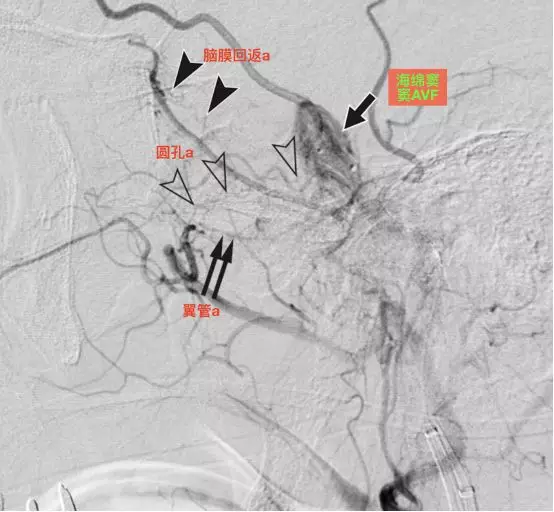

a,左侧颈外动脉造影侧位,显示海绵窦硬脑膜动静脉瘘(单箭),由脑膜回返动脉(实箭头),圆孔动脉(空箭头)和翼管动脉(双箭)供血(Tanoue 2013)。

左侧颈外动脉3d-DSA侧位,显示海绵窦硬脑膜动静脉瘘(单箭),由脑膜回返动脉(实箭头),圆孔动脉(空箭头)和翼管动脉(双箭)供血(Tanoue 2013)。